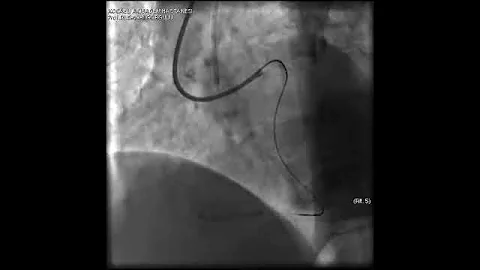

Aortic Dissection And Radial Rupture During Retrograde Cto Pci: Management Of Complications Vİdeo 25